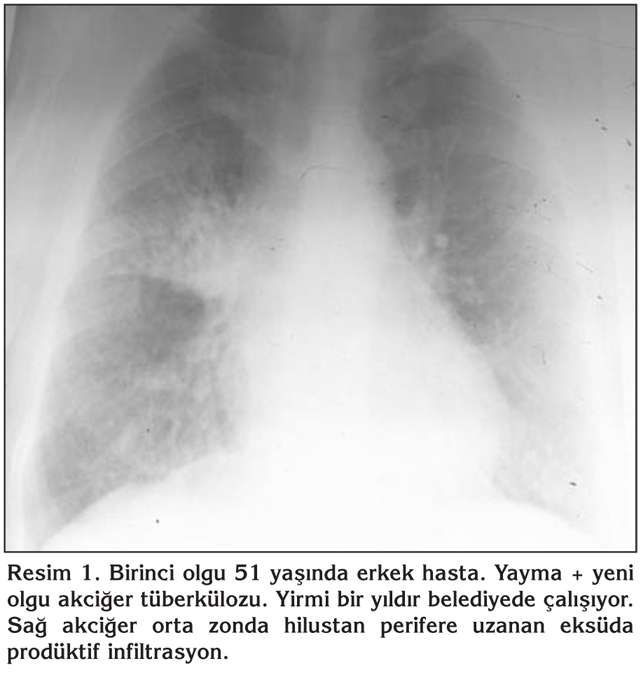

Akci?er t?berk?lozu ??phesi olan 12 olgu incelendi?inde; iki olgu yayma pozitif yeni olgu akci?er t?berk?lozuydu. Bunlardan birinci olgunun mikrografisinde sol akci?er ?st zonda eks?da prod?ktif lezyon, ikinci olgunun ise sa? akci?er hiler b?lgeden perifere uzanan zonda eksuda prod?ktif infiltrasyan mevcuttu (Resim 1,2). Her iki olgu da b?lgede ikamet ediyordu, g?? etmemi?lerdi. Aralar?nda akrabal?k yoktu. Bir olgu 6 y?l, di?er 21 y?ld?r ?of?r olarak ?al???yordu. Be? olgunun daha ?nce t?berk?loz tedavisi ald??? ve tedaviyi tamamlad??? (4 olgu akci?er, 1 olgu plevra t?berk?lozu) tespit edildi. Di?erleri; bir olgu akci?er kanseriydi ve tan?dan bir y?l sonra vefat etti. ?ki olgu pn?moni, bir olguda akci?erde patoloji saptanmad?, di?er olguda meniskus operasyonundan sonra akci?er embolisi geli?ti?i ??renildi (Tablo 2).

Resim 1